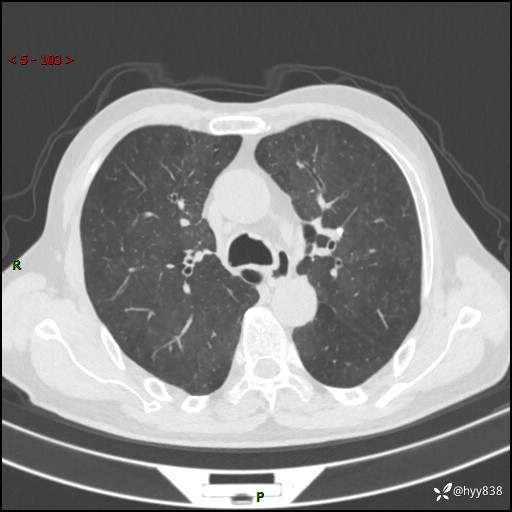

辅助检查:CT

胸部CT平扫